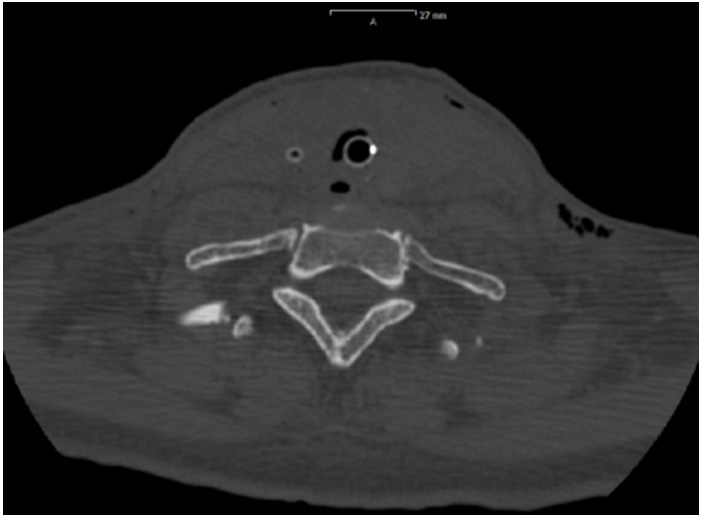

Figure 4: Postoperative CT-scan: neck area heavily edematous.

figure 4